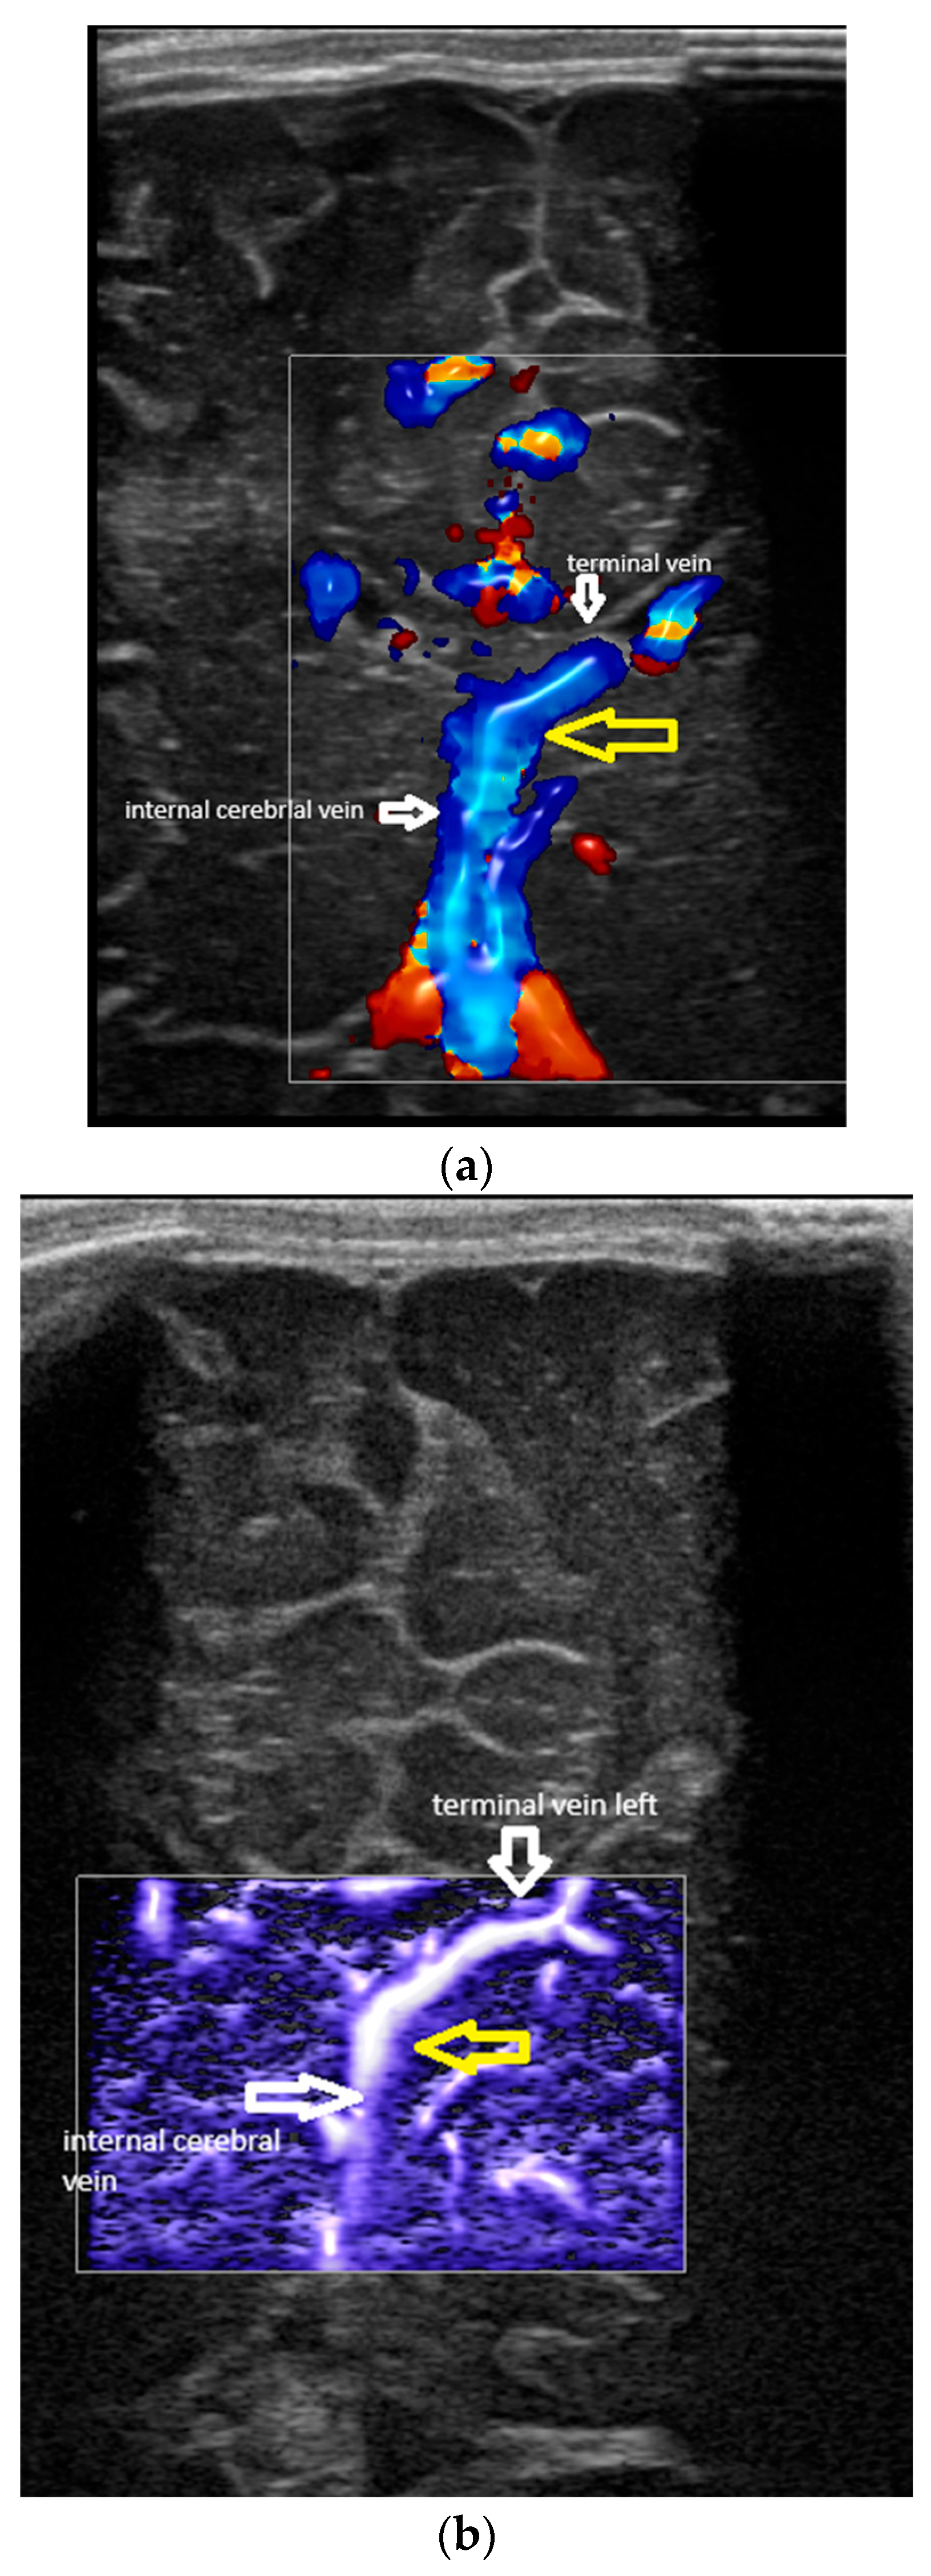

- Confluence at the level of the foramen of Monro (Figure 2).